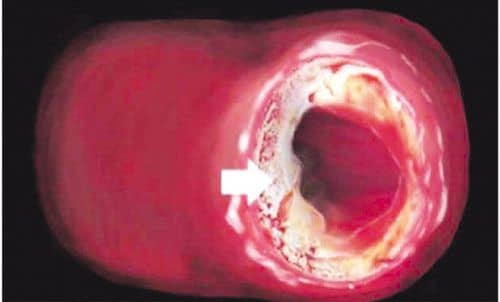

A trigliceridek kevésbé közismert vegyületek, melyek szintén felelősek a szívinfarktus megnövekedett kockázatáért. Néhány szakértő úgy véli, hogy a trigliceridek még a koleszterinnél is fontosabb kockázati tényezőt jelentenek. A vérben jelenlévő trigliceridek magas szintje növelheti az infarktus okozta halál veszélyét, mivel hatása miatt a vér sűrűbbé, viszkózusabbá válik, nehezebben préselődik keresztül az összeszűkült ereken, és hajlamosabb rögöket formálni.Az omega-3 többszörösen telítetlen zsírsavak képesek döbbenetesen csökkenteni a trigliceridszintet (harminc százalékkal), s így ismételten csökkentik a szívinfarktus kockázatát.A rostok és a szívelégtelenség kapcsolataA táplálékban található rostok aktívan hatnak a koleszterin ellen. Azért, mert a rostok hajlamosak a bélben megkötni a koleszterint, ezáltal akadályozva felszívódását a szervezetbe. A rostok másik előnye, hogy segítik a bélbaktériumok szaporodását, melyek közül néhány a koleszterolt rosszul felszívódó anyagokká bontja le.A növényi táplálékokban jelen van egy másik anyag is, mely – szinte szó szerint – természetes koleszterinsemlegesítő. Ez a vegyület a béta-szitoszterin, tulajdonképpen a koIeszterin növényi megfelelője. Azon kívül azonban, hogy sokkal kevésbé káros, mint a koleszterin, a béta-szitoszterin megakadályozza, hogy a koleszterin felszívódjon a belekben. Mégpedig azáltal, hogy versenyre kel a koleszterinnel n bélfalon található megfelelő felszívóhelyekért. A szervezet a béta-szitoszterint „összetéveszti” a koleszterinnel, megpróbálja felszívni, de rájön, hogy nem sikerül, ezért a bétaszitoszterin újra felszabadul. Ezalatt azonban a koleszterol emésztetlenül áthatol a testen. Sajnos a modern olajsajtolási technológia ennek az értékes anyagnak a nagyrészétől „megszabadítja” a végterméket.